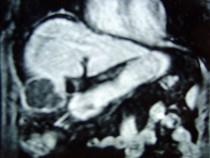

问题 男性,60岁,右上腹胀不适,右肝区叩击痛,影像检查如图,最可能的诊断是 ( )

选项 A.肝硬化 B.肝硬化、再生性肝癌 C.肝硬化、腹腔间质瘤 D.肝硬化、膈下脓肿 E.肝硬化、结节性增生

答案 B